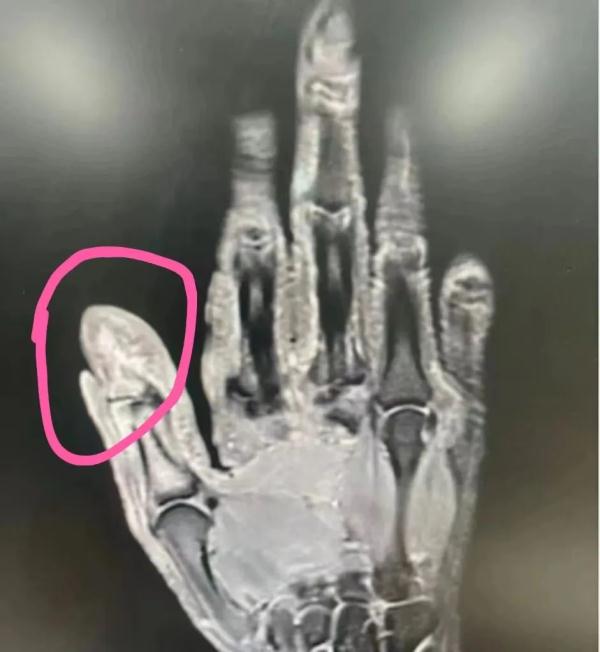

接诊的卢医生为郭大叔进行详细检查后,发现其左手大拇指严重感染,甚至已经侵犯指骨。

手术过程中,医生发现郭大叔的指骨已经被部分破坏,如果进一步发展下去,可能发展为骨髓炎,甚至会有截指的风险。